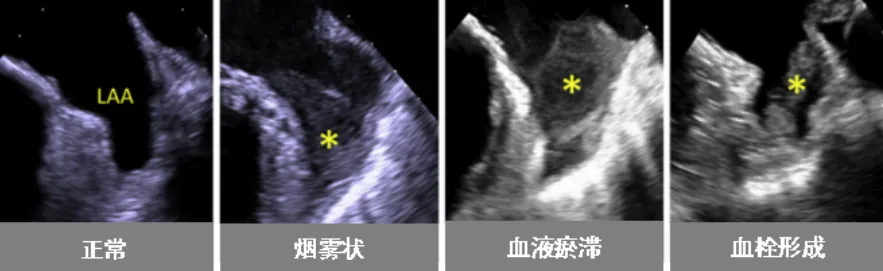

近日,糖心vlog (简称中山一院广西医院)超声医学科联合心血管内科为一名心脏病患者开展了经食管超声(TEE)检查。该项技术的开展,填补了我院在经食管超声领域的空白。患者黄阿姨(化名)今年59岁,几年前被诊断为“风湿性心脏病-二尖瓣中度狭窄”。近日,黄阿姨在医院复查心脏超声,报告提示风湿性心脏病-二尖瓣中度狭窄并中度关闭不全,且有左心耳附壁血栓形成可能(约3cm,游离端活...